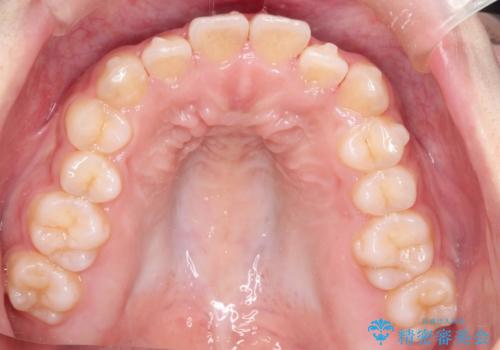

インビザライン 前歯のがたつきを目立たず矯正

- 前歯のがたつきが気になるとのことで来院されました。

インビザラインにて治療を行いました。

わずかに歯と歯の間に隙間を作り、歯列矯正を行いました。

マウスピースをしっかりと使用していただけたので、スムーズに治療を終了することができました。